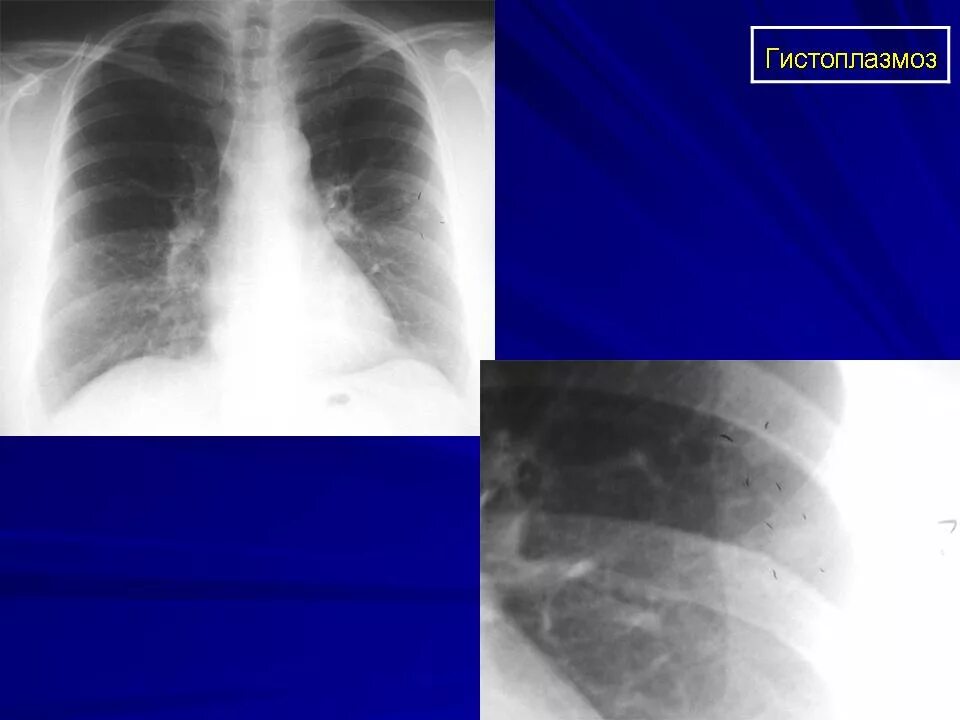

Гистоплазмоз это